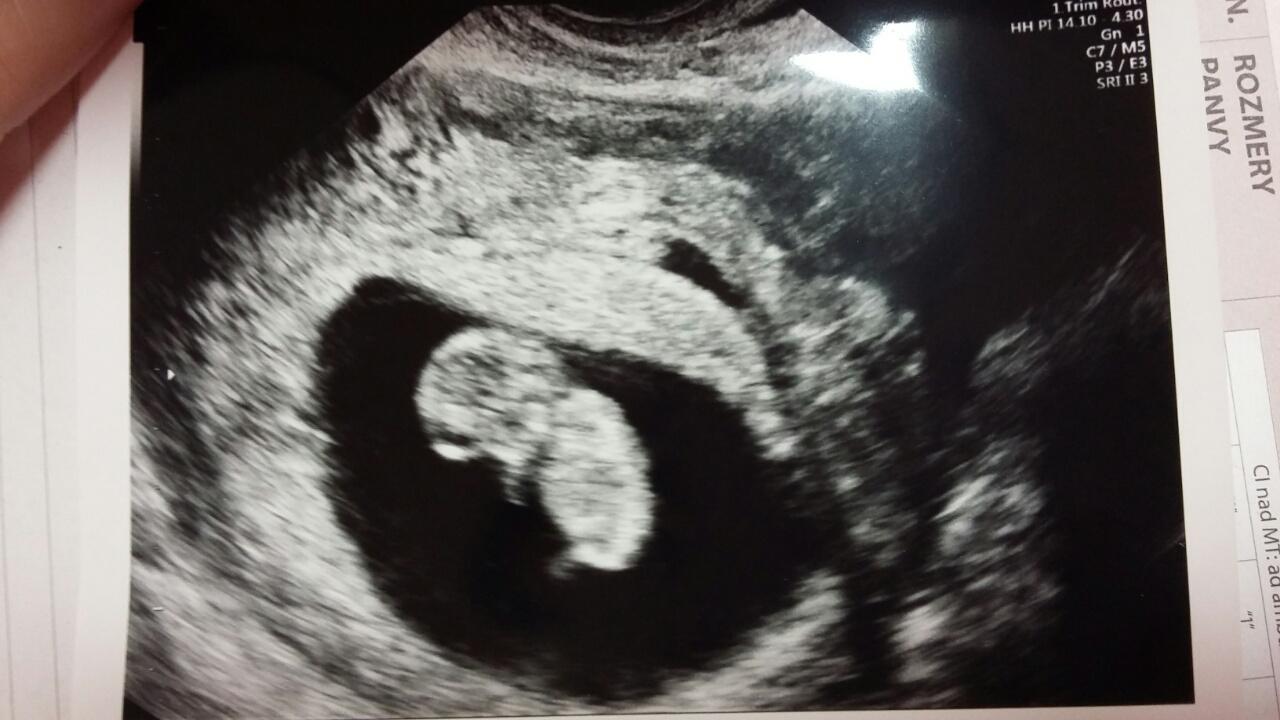

@anitu ahoj srdiecko este dr nevidel mam ist v pondelok znovu 😕 uvidíme

@andreasmola ahoj.ja som babo videla a uz aj srdiecko🙂) ale jej pristup sa mi nepacil.nespytala sa ma na nic ci mam nejeke tazkosti,som jej povedala ze dvihame tazke trubky a zvaram v robote s tie vypary tam,a ona ze ma nemoze vypisat.no co uz.nevadi.som stastnaa🙂